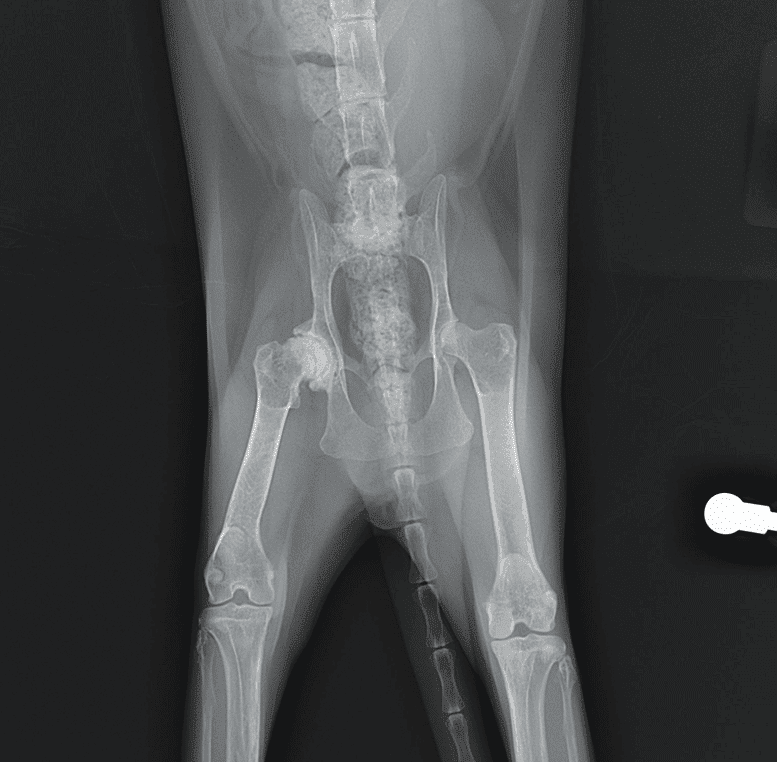

Radiografías: el papel de la imagenología en la detección de osteoartritis

Las radiografías son una herramienta fundamental en la imagenología, especialmente en la detección de la osteoartritis. Este tipo de artritis, que afecta a las articulaciones, puede ser difícil de diagnosticar en sus primeras etapas. A través de las radiografías, los veterinarios pueden obtener una visión clara de los cambios estructurales en las articulaciones de los animales, lo que facilita un diagnóstico más preciso.

- Visualización clara: Permiten observar la pérdida de cartílago y la formación de osteofitos, que son características clave de la osteoartritis.

- Detección temprana: A través de la identificación de cambios sutiles en la articulación, se puede intervenir antes de que la enfermedad progrese.

- Evaluación de múltiples articulaciones: Se pueden realizar radiografías de diferentes partes del cuerpo en una sola sesión, lo que ahorra tiempo y recursos.

- Visualización de tejidos blandos: Las radiografías son menos efectivas para evaluar los tejidos blandos, como los músculos y los ligamentos, que pueden estar involucrados en la osteoartritis.

- Variabilidad en la interpretación: La experiencia del veterinario juega un papel crucial en la interpretación de las imágenes, lo que puede llevar a diferencias en los diagnósticos.

Radiografías

Las radiografías son esenciales para visualizar el estado de las articulaciones y los huesos. Aunque son más conocidas por su uso en el diagnóstico de osteoartritis, también ayudan a descartar otras afecciones como:

- Fracturas: Lesiones óseas que pueden causar dolor y movilidad reducida.

- Tumores: Crecimientos anormales que podrían estar afectando la movilidad del gato.